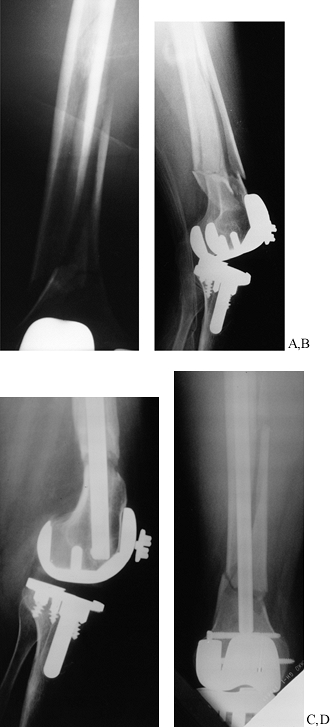

![]() |

Figure 20.7. Femoral fracture treated with antegrade, closed, locked intramedullary nailing. A: AP radiograph showing fracture. B: Lateral radiograph. C:

Postoperative AP radiograph. Note the cross-locking screws about the lesser trochanter and, distally, the bicortical cross-locking screws. The fracture is in excellent alignment. D: Lateral radiograph. |